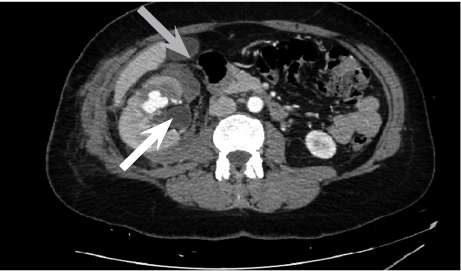

Right femoral artery was punctuated under local anesthetic. Inferior segmental artery was selectively cathe­terized and pseudoaneurysm was visualized. A microcatheter was inserted into segmental branch (Figure 4).

Figure 4. Renal pseudoaneurysm catheterized and visualized using contrast solution